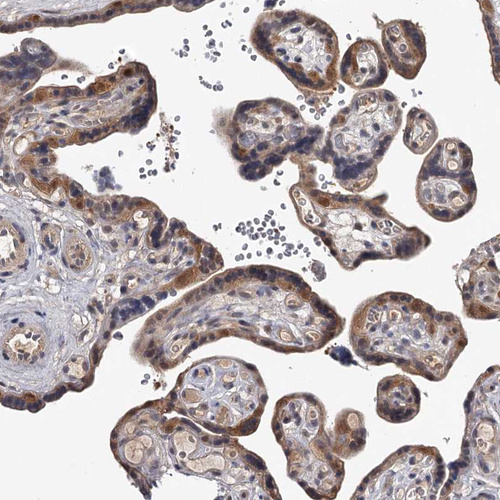

Immunohistochemical staining of human testis shows strong cytoplasmic positivity in cells in seminiferous ducts.